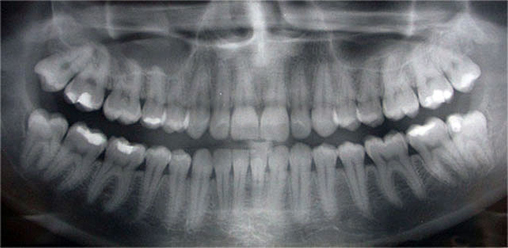

Digital Radiography Brampton

Digital radiography is a type of X-ray imaging that uses digital X-ray sensors instead of traditional photographic film. This method allows us to take out x-rays with almost ninety percent reduced exposure to harmful radiation. Moreover, the image quality helps in analyzing and seeing things more clearly.

The process does not take more than one appointment. Digital radiography involves inserting a sensor inside your mouth to capture images of your gums and teeth. This electronic devise is also connected to our computer, enabling instant depiction of x-rays on our computer screen, with no development step in the middle.

It is almost impossible to practice dentistry without using x-ray technology. Digital radiographs allow us to diagnose and treat oral problems not yet visible to the humkan eye, including gum disease, early tooth decay, abnormal growths and abscesses. There is absolutely no doubt that since state-of-the-art x-rays have become available, we have been able to save countless teeth.